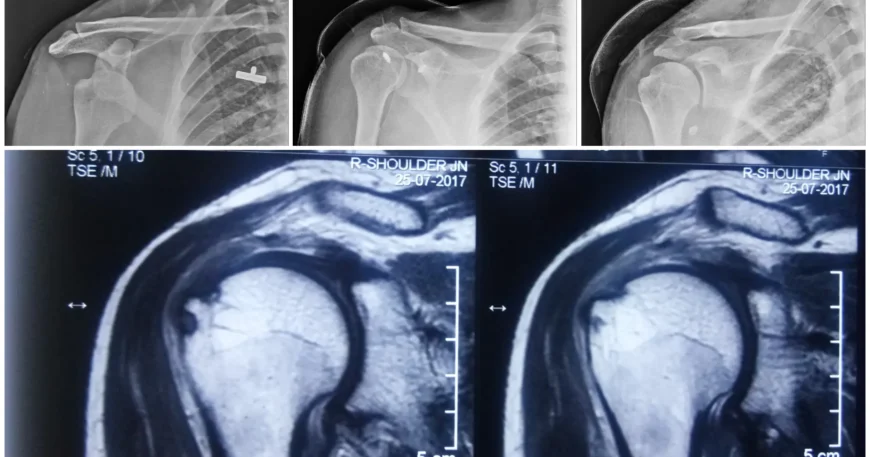

Shoulder Biceps Tendon Disease & Bankart Repair

Advanced Shoulder Surgery at Balanku Hospital

The shoulder is a complex and highly mobile joint that relies on strong tendons and ligaments for stability and smooth movement. Injuries, overuse, or trauma can affect key structures such as the biceps tendon or the shoulder labrum, leading to pain, weakness, and recurrent dislocations.

At Balanku Hospital, our orthopedic and sports medicine specialists provide advanced, minimally invasive treatments for Shoulder Biceps Tendon Disease and Bankart lesions, helping patients regain comfort, strength, and confidence in shoulder movement.